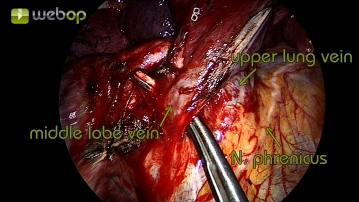

Präparation der Mittellappenvene

Nach Darstellung der Pulmonalarterie und Resektion der Parenchymbrücken erfolgt jetzt die Präparation am Lungenhilus. Die obere Lungenvene zeigt sich im Situs bereits ohne weitere Präparation. Für gewöhnlich drainiert die Mittellappenvene in die obere Lungenvene und kann dort eindeutig identifziert werden. Der Verschluss erfolgt hier mittels TitanClips.